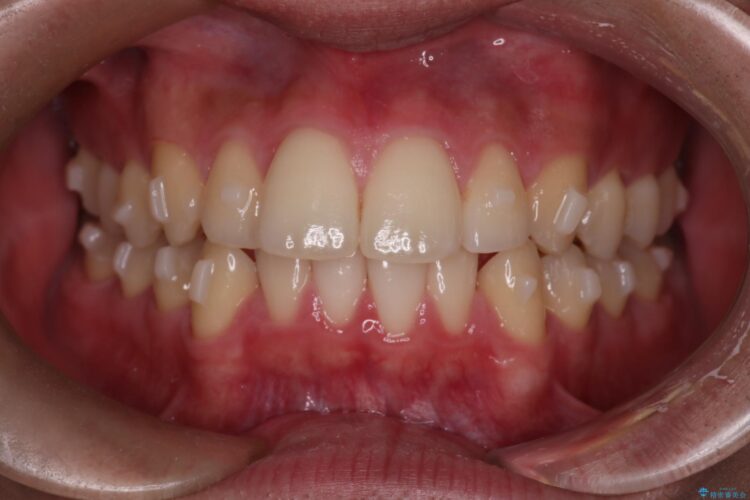

上の前歯が出ているのが気になるとご来院された患者様です。

患者様はシミュレーション通りに歯が動くのかと心配されていました。

可能な限り計画通りに歯を動かすために、マウスピース1枚あたりの使用時間を長めに使っていただきました。

そのため、多少治療期間が延びましたが、リファイメント(マウスピースの再発注)なしで終了することができました。